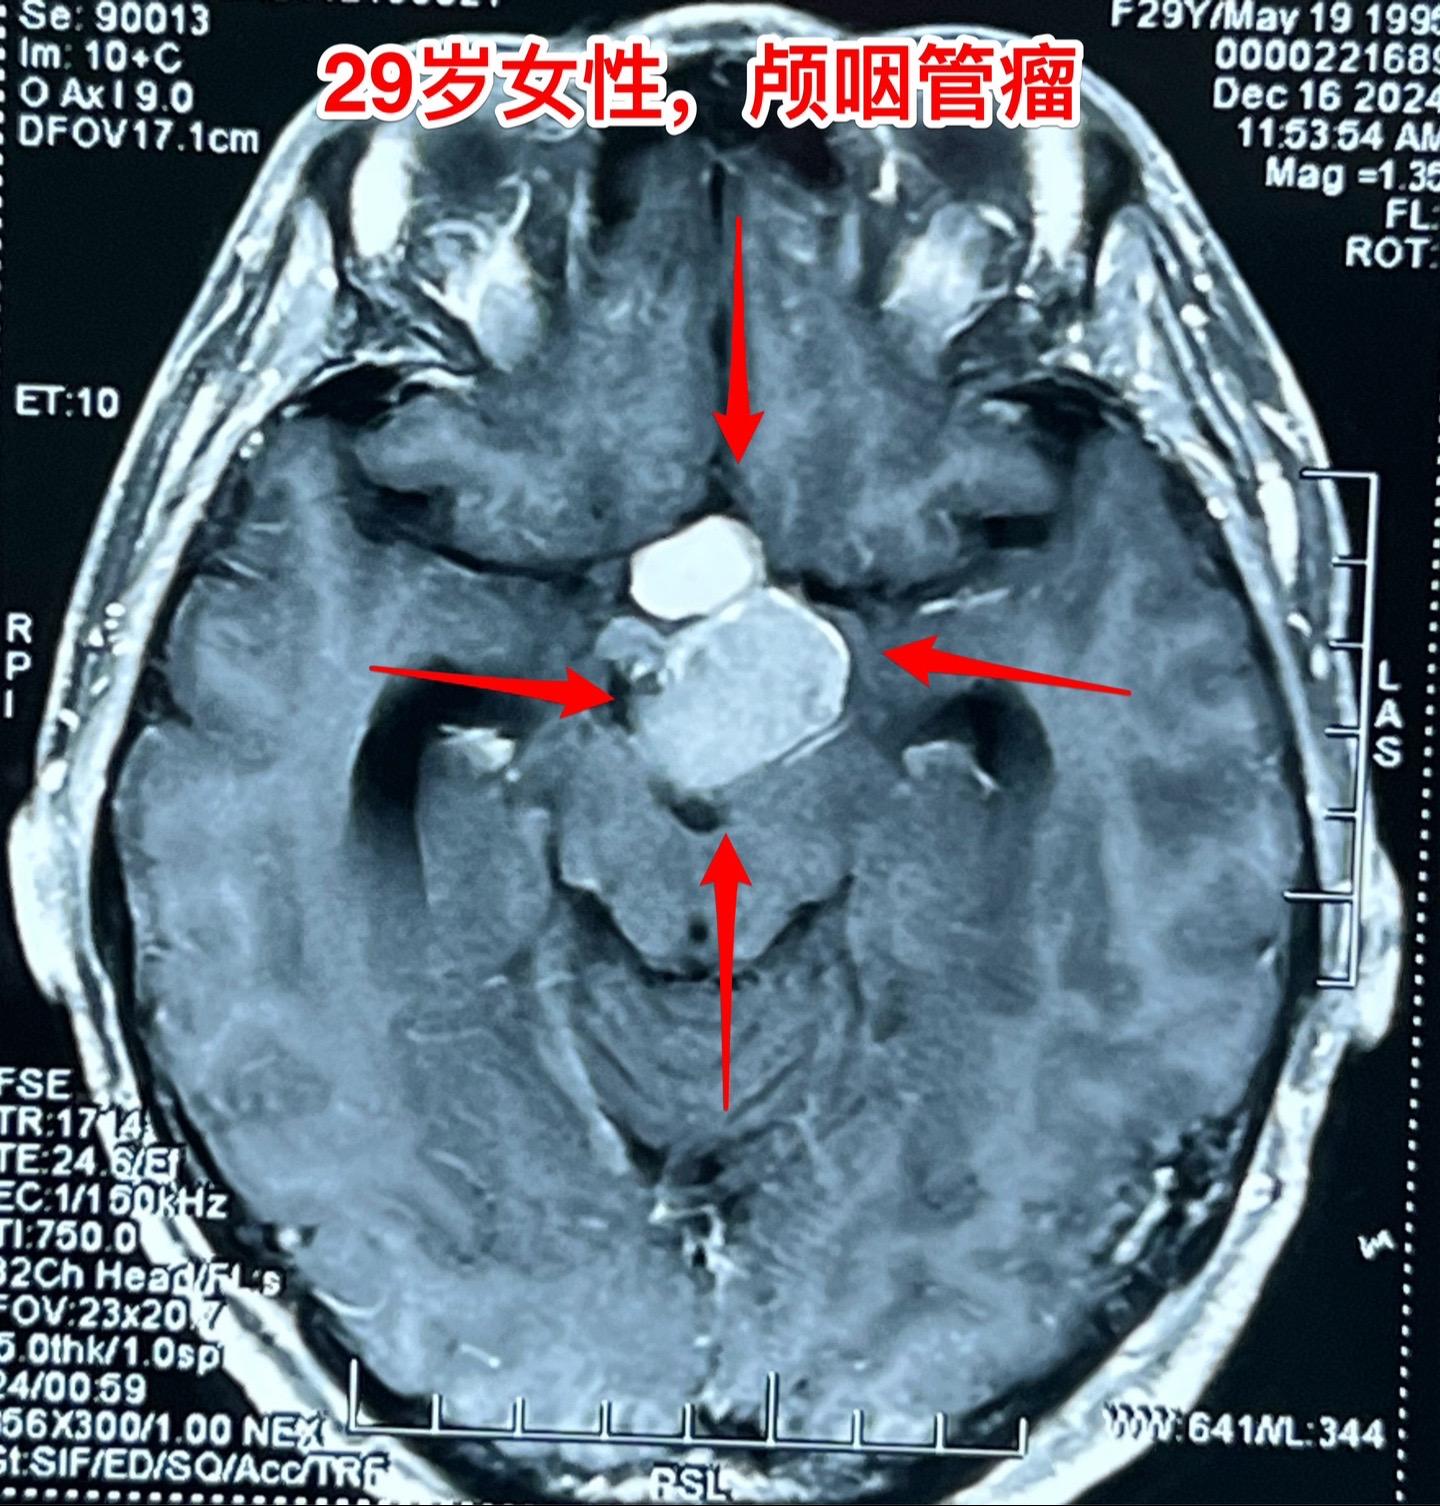

大理市女教师患颅咽管瘤。29岁大理市女老师,因头晕,内分泌功能障碍到医院行脑部CT及磁共振检查,发现颅咽管瘤。CT显示肿瘤有钙化,是典型的造釉细胞性颅咽管瘤。 患者家人系医务工作者。发现颅咽管瘤后即来北京就医。到我院检查视力视野,有视野缺损。 今日在我科作了颅咽管瘤切除手术,手术后5小时病人即清醒了。肿瘤完全切除,垂体柄结构完整,漏斗保留约三分之一。